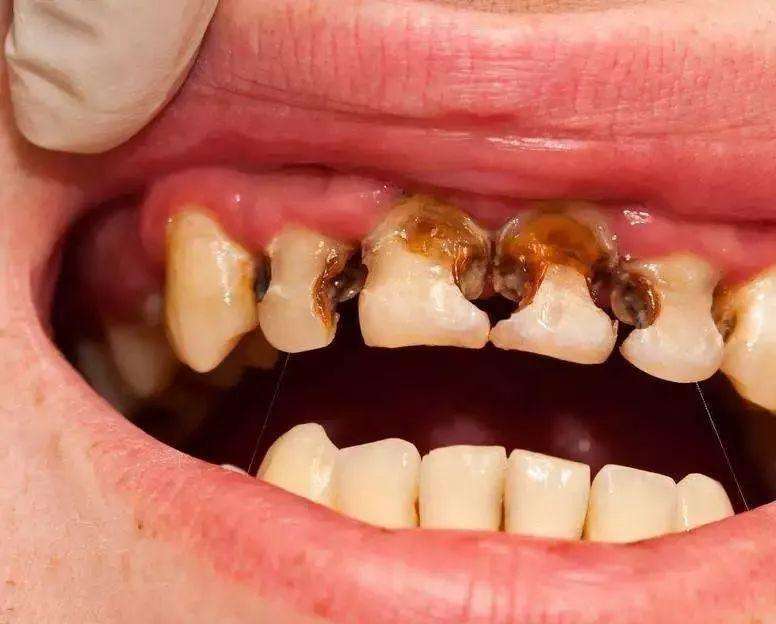

什么是根管治疗呢?所谓根管治疗,又称牙髓治疗,是治疗根尖周病或牙髓病最有效的技术。它通过清除根管内的坏死物质和发炎的牙髓,并进行适当的消毒,填充根管,以去除根管内的容物对根尖周围组织的不良刺激。根管治疗这种治疗方式不仅使牙齿得以保留,还能与拔牙术互补呢!一般牙齿因龋齿有洞,外部细菌侵入到牙髓腔,导致牙髓受到细菌感染而发炎的或是细菌侵入牙槽骨里,引起牙根尖周围组织发炎的,都需要进行根管治疗。

根管治疗也不同于过去所说的”杀神经“。在以前,如果遇上牙髓发生炎症,引发疼痛,一般会采用将牙齿钻开,使用药物将牙齿内部发炎的牙髓统统杀死,从而缓解疼痛。但随着治疗观念的全面革新和现代口腔医学技术的进步,这种老套的方法逐渐被淘汰。相比于”杀神经“,根管治疗的修复效果会更彻底,能进行更加彻底的清理和严格的消毒,并用人工的充填材料将”根管“严密填塞。